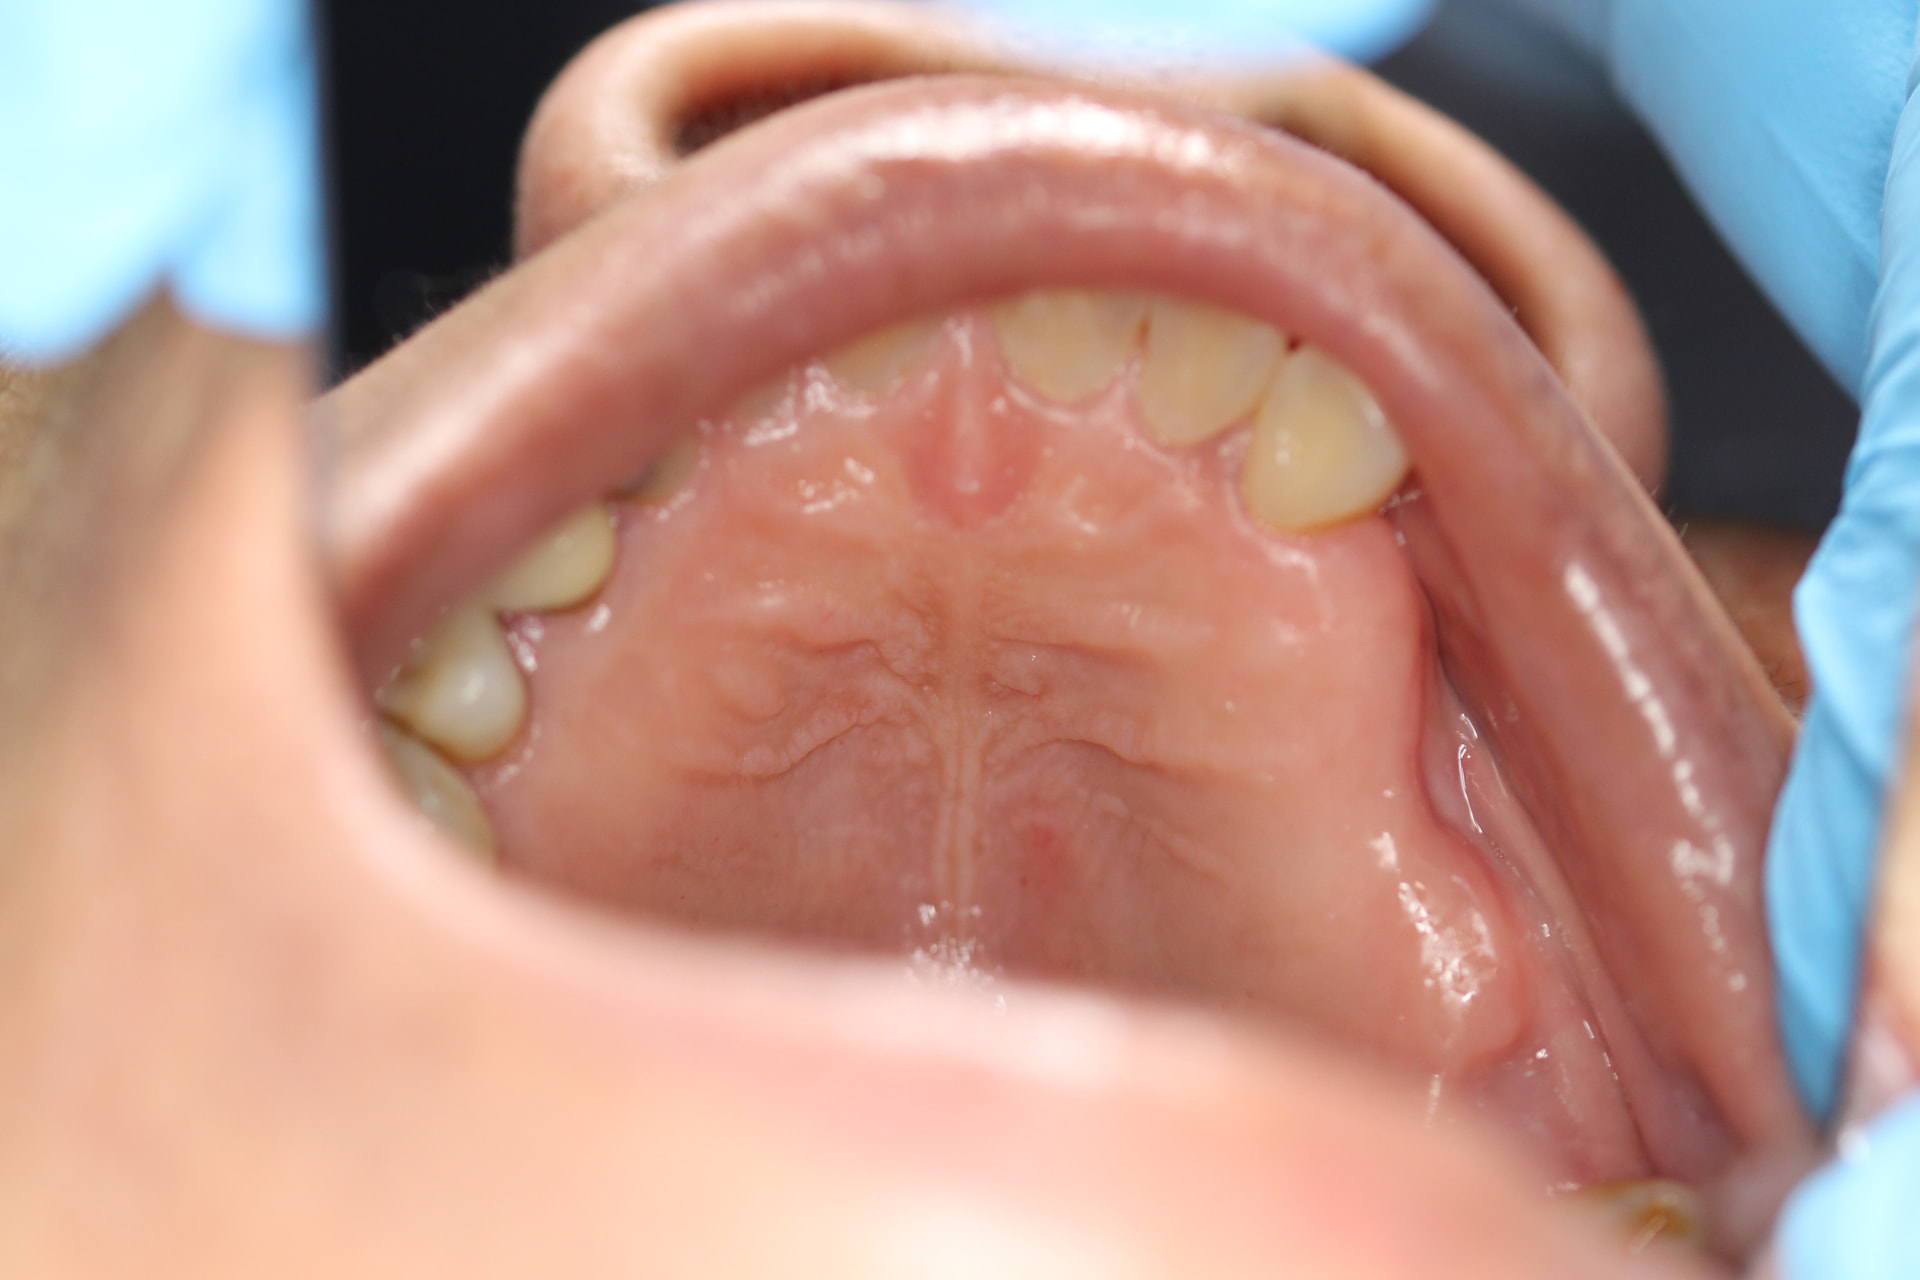

after 2 months of healing:

i plan to keep the 2mm of connective tissue on the buccal flap , because the bio guide membrane needs to stay on the hard sound bone rather than defect of previous extraction site (with less sound bone), not sure if you guys agree with the flap design, the proximal gingival papillae was preserved as there is some recession on UR7 , which would make suture difficult.